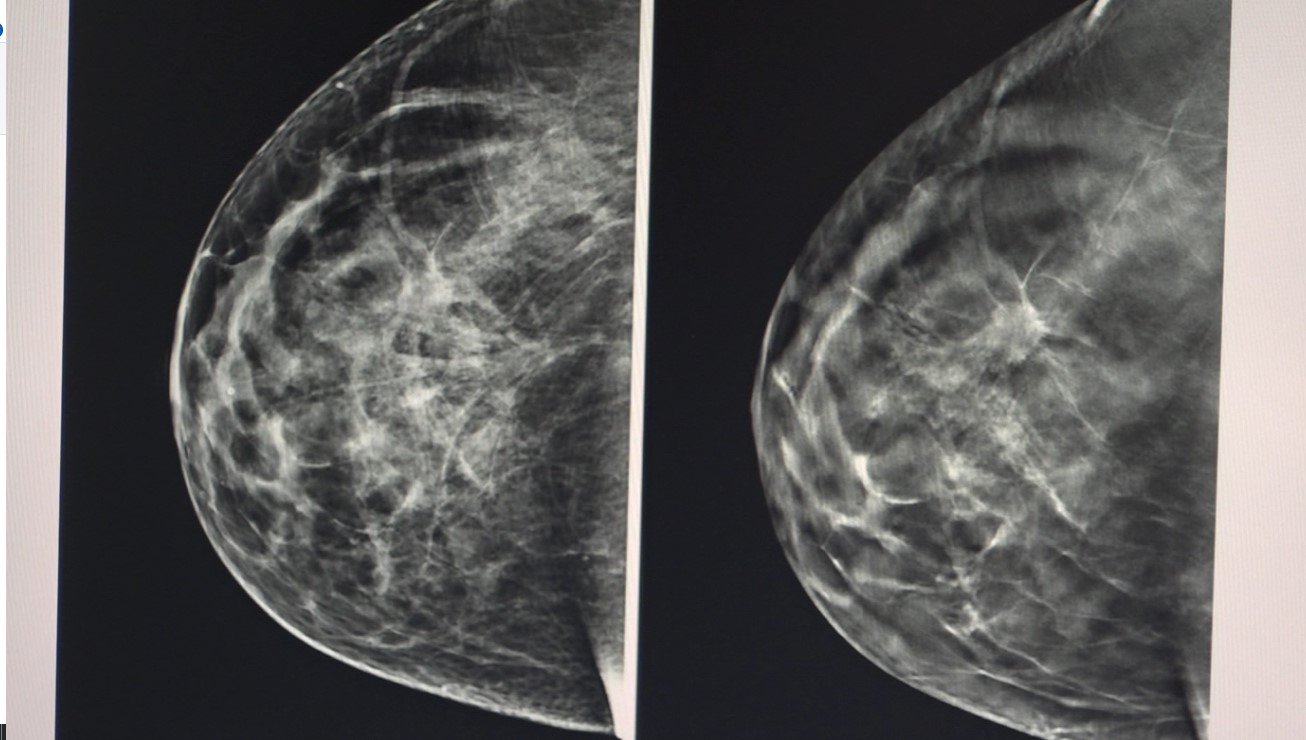

El cáncer de mama es el más común entre las mujeres: más de 2.3 millones de casos al año se presentan en el mundo según la OMS y cerca de 15 mil en Colombia. Pero, cuando se detecta a tiempo, la supervivencia puede llegar al 90%.